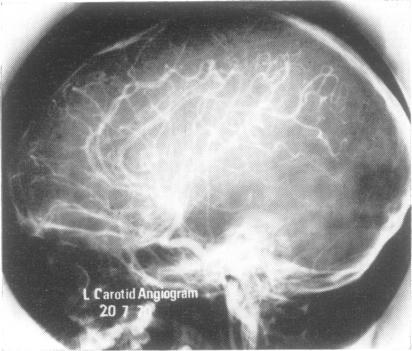

Two patients with Herpesvirus hominis (herpes simplex) encephalitis were investigated by serial isotope encephalograms using technetium-99m pertechnetate. In the first case the diagnosis was made by brain biopsy, and by successful tissue culture, and was confirmed by a significant rise in antibody titre, but in the second the laboratory evidence was exclusively serological. Necrotizing encephalitis was presumed in both cases because the illness was grave and focal signs developed in conjunction with radiological and electroencephalographic evidence of circumscribed lesions of the hemisphere. The emergence of new lesions in the brain scan at a time of clinical remission was found to be a warning of impending relapse. Such lesions had to be distinguished from areas of increasing uptake of isotope due only to local change in vascular permeability. Decay of EEG activity together with clinical signs of focal abnormality over an area of isotope concentration indicated a necrotizing lesion. Cytosine arabinoside (cytarabine), an alternative to idoxuridine as an antiviral drug, was used in both cases. A third patient, suspected in life of having a degenerative encephalopathy, was found at necropsy to have necrotizing encephalitis. Herpes infection though probable was not confirmed. The most severe lesions were in the frontal and temporal lobes, which had shown increased uptake of technetium in the encephalogram performed six weeks before her death.

对两名人疱疹病毒(单纯疱疹)脑炎患者进行了连续同位素脑扫描检查,使用的是高锝[99mTc]酸盐。第一例患者通过脑活检和成功的组织培养做出诊断,并通过抗体滴度显著升高得到证实,但第二例患者的实验室证据完全是血清学的。两例均推测为坏死性脑炎,因为病情严重,且出现局灶性体征,同时伴有半球局限性病变的放射学和脑电图证据。发现在临床缓解期脑扫描中出现新病变是即将复发的警示。此类病变必须与仅因局部血管通透性改变而导致同位素摄取增加的区域相区分。脑电图活动减弱以及在同位素浓聚区域出现局灶性异常的临床体征提示存在坏死性病变。两例患者均使用了阿糖胞苷作为抗病毒药物,替代了碘苷。第三例患者生前怀疑患有退行性脑病,尸检发现为坏死性脑炎。虽然可能存在疱疹感染,但未得到证实。最严重的病变位于额叶和颞叶,在其死亡前六周进行的脑扫描中显示这些部位的锝摄取增加。